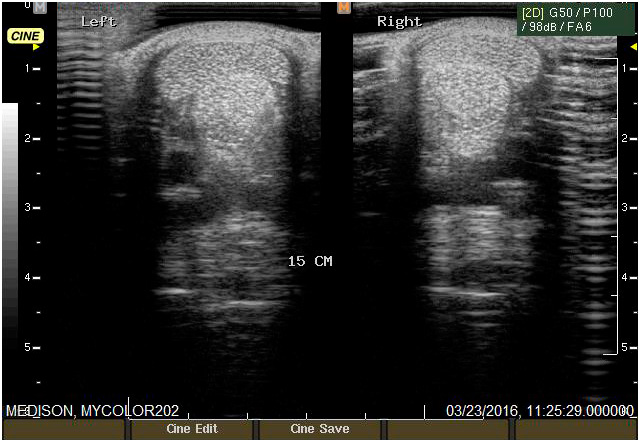

Ecografía

Cuenta con Ecografía digital de alta complejidad.

17 años de experiencia siendo una de las ecografistas más reconocidas en la práctica de equinos. Realiza pasantías en la universidad de Davis California y en Mid-Atlantic Equine Medical Center en New Jersey.